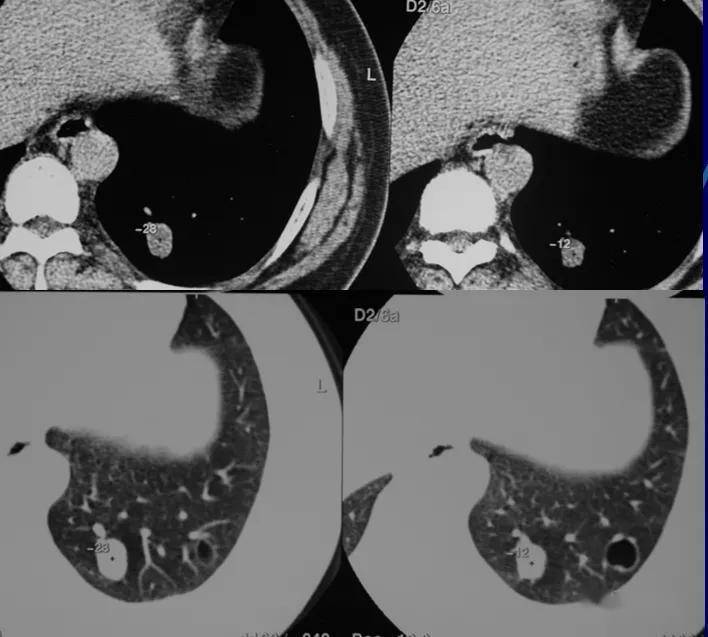

支气管结石,你见过吗?

病例肺里的小石头是怎么来的

听过肾结石,胆结石,咋还有肺结石?| chest病例_网易订阅